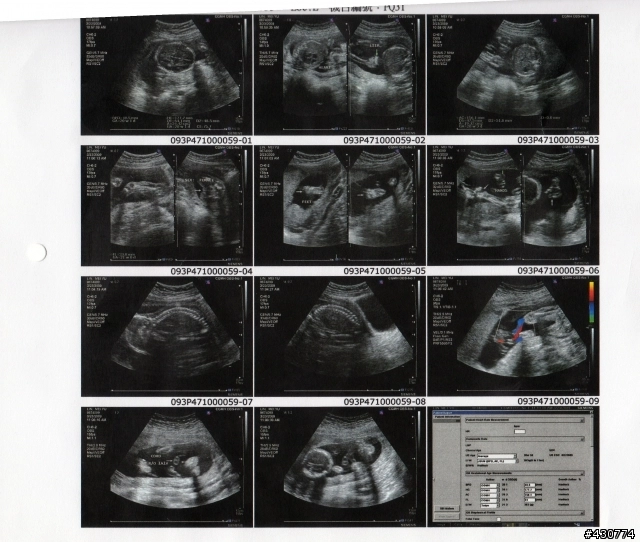

Q寶寶29w2d 台大醫院高層次超音波檢查 施爸拍拍寫寫過生活 隨意窩xuite日誌